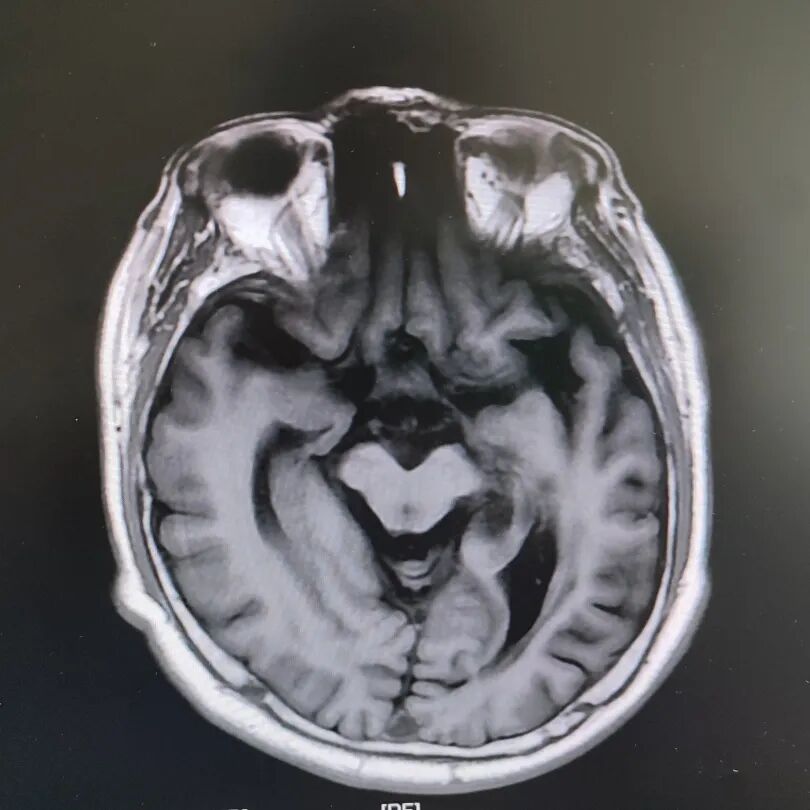

患者頭部磁共振影像